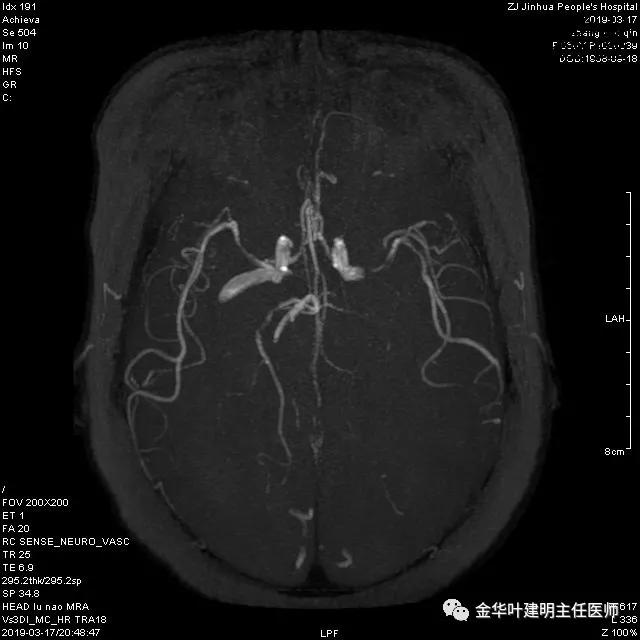

章某有高血压病史多年,平时血压控制的也不规范。术前我们予以控制血压,并常规检查头颅MRA,结果却发现了意外的合并问题:

报告提示左侧大脑中动脉M1段及左侧大脑后动脉P1段管腔闭塞。按影像科的建议并请神经内科会诊后,予以行CTA检查。结果如下:

可见其左侧大脑中动脉起始部管腔重度狭窄,右侧大脑中动脉近段管腔也有狭窄;左侧大脑后动脉中远段未见显影。又建议其DSA检查。我们仔细询问章某平时没有神经系统的症状,回忆起来说大概3年前有段时间头昏比较明显,但也没有到大的医院详细检查,后来自行改善。鉴于平时并无明显症状,我们认为其脑血管的病变是慢性闭塞,并已经有侧支代偿。便先请神经外科会诊,会诊后的意见是可以先处理肺部疾病,待情况稳定后再到神经外科进一步诊治。这样,我们便打算为其进行手术。当然因为上叶病灶考虑良性,且位置靠肺外周部位,而下叶病灶考虑恶性,又是中肺叶中央,无法亚肺叶切除,况且病灶大于3厘米,密度虽还是混合磨玻璃,但已经明显偏向实性。所以拟定手术方式是“胸腔镜下左肺下叶切除+上叶楔形切除及纵隔淋巴结清扫术”,当然万一上叶也是恶性,也只能同样是这样的手术方式,全肺切除显然风险过高。